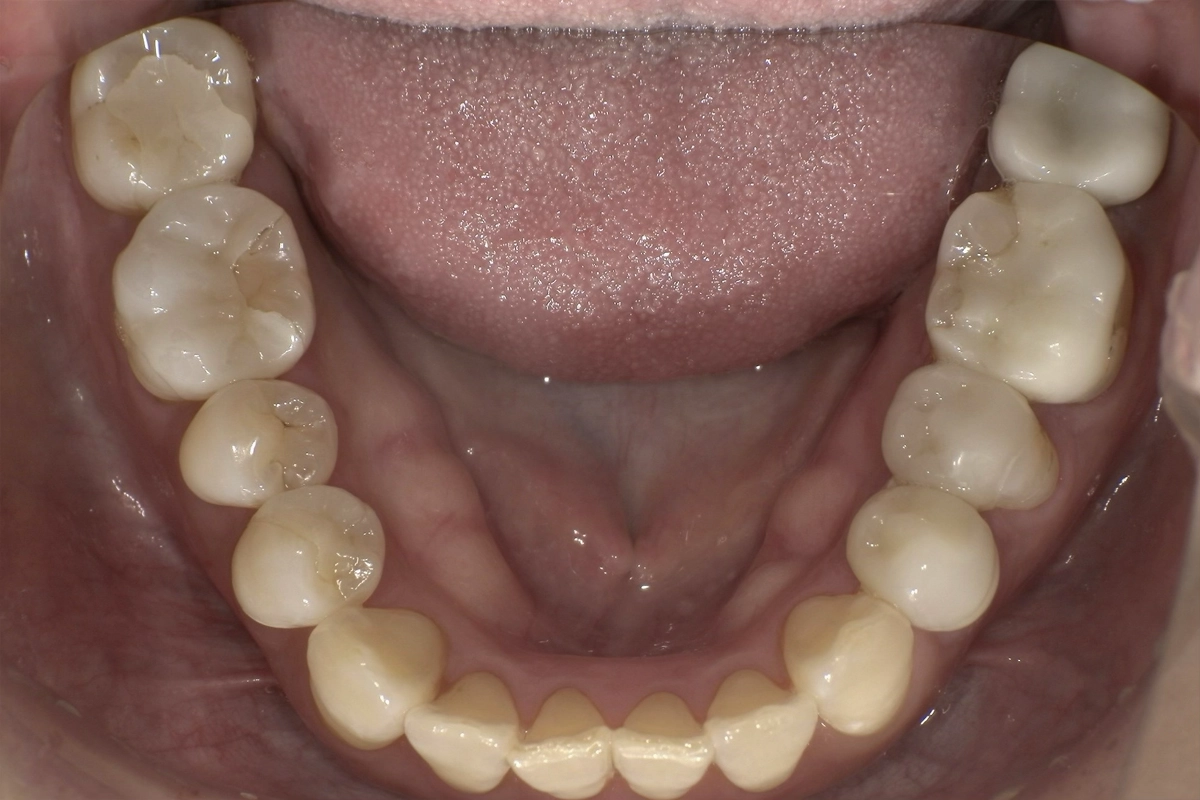

特に下の前歯は歯同士が重なり合い、一部の歯が前後にずれて不規則に並んでいる状態でした。

歯が重なった部分には歯ブラシの毛先が届きにくく、実際に歯と歯の間に歯石の沈着も確認されました。

上の前歯にも軽度の乱れがあり、左右の側切歯から犬歯にかけて歯列のアーチが崩れていました。

治療前の写真では、下の前歯の歯頸部(歯と歯茎の境目)に歯石の付着が見られ、清掃が行き届いていないことがうかがえます。